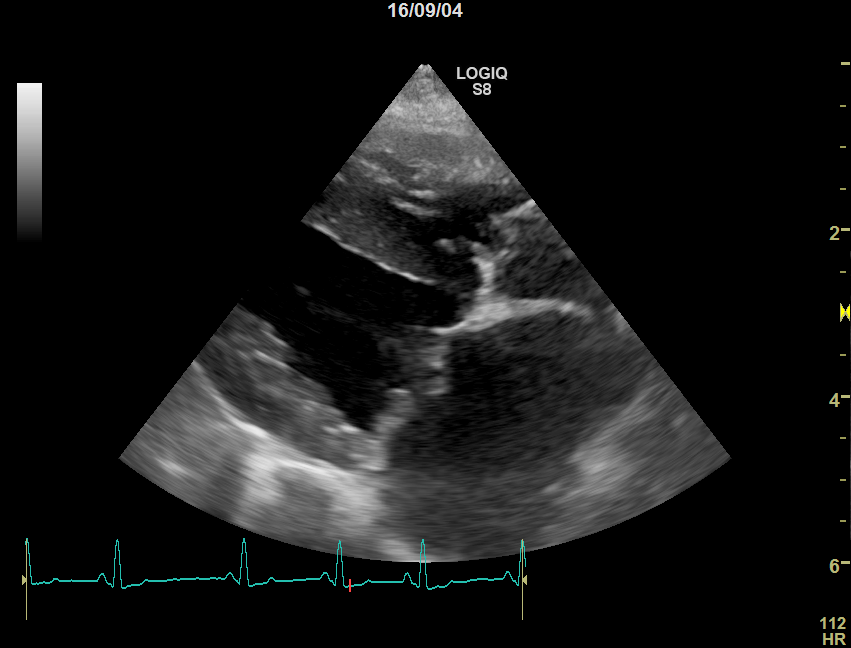

②心臓超音波検査

心臓の機能的評価を行います。

心臓内部の弁の逆流や狭窄が生じていないかどうかを確認し、同時に心房心室の拡大や心筋壁の肥大を評価します。

また、猫では血栓がないかどうかを見ています。

正常な猫

心臓病(肥大型心筋症)の猫

肥大型心筋症の猫では左心室の壁が厚くなり、内部が狭くなっているのが分かります。